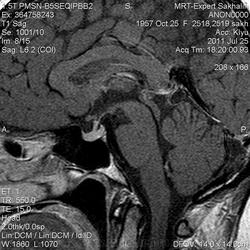

Как мы "динамичим"гипофиз

Женщина.6 лет назад выявлено образование левой доли нейрогипофиза.Пришла на контроль.

Постконтраст

Мне самой показался случай не совсем ясным, но динамик четко показывает участок с отставанием в контрастировании, воронка смещена вправо-о чем  думать бедному начинающему специалисту?